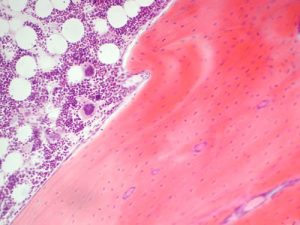

Dopo la nascita i tessuti emopoietici sono rappresentati dal midollo osseo rosso, che è capace di generare vari tipi di cellule che andranno a comporre la parte corpuscolata del sangue

Esso si differenzia dal midollo osseo giallo, che ha perso questa capacità. Il midollo osseo rosso è situato, nell’adulto, nelle epifisi delle ossa lunghe, corte e piatte.